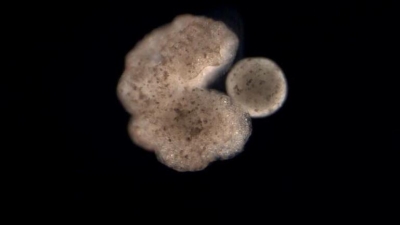

Σημαντική εξέλιξη: Τα πρώτα ρομπότ του κόσμου που έμαθαν να αναπαράγονται 30/11/2021 - 18:37 - Διεθνή